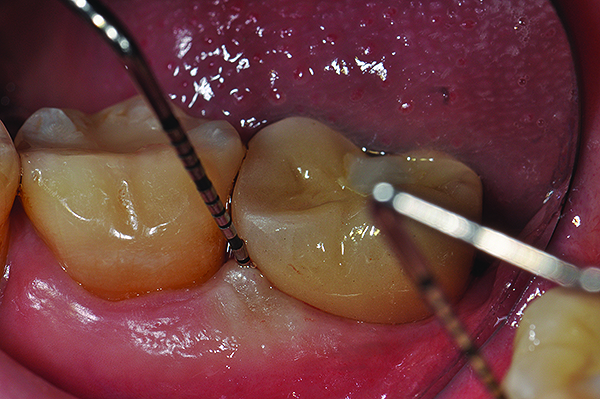

Fig 5. Radiograph of a mandibular left first molar implant in a 61-year-old man taken 2 years after the implant’s placement. No bone loss beyond physiologic remodeling has occurred.

Figure 5

Fig 6. Clinical view of this area suggests that peri-implant mucositis is present, as there is bleeding on light probing and inflammation of the tissue.

Figure 6